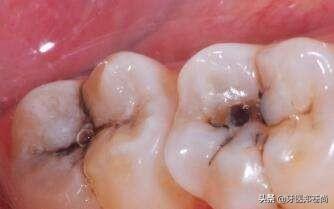

现在有很多的宝宝从小就因为吃糖过多或者不注意口腔清洁卫生导致蛀牙了,令很多家长比较担忧,那么小孩子蛀牙要不要拔掉呢?小孩子蛀牙疼怎么办?接下来和小编一起来看看吧。

孩子的牙齿疼痛一般是龋齿引起的,如果是乳牙长了蛀牙,还没有到替牙期,尽量治疗保留,是不太建议拔牙的,因为过早拔掉乳牙会影响恒牙的正常萌出,严重的话可能会影响咀嚼功能,咀嚼颌力通过乳牙,刺激颌骨生长发育;乳牙能引导恒牙萌出。